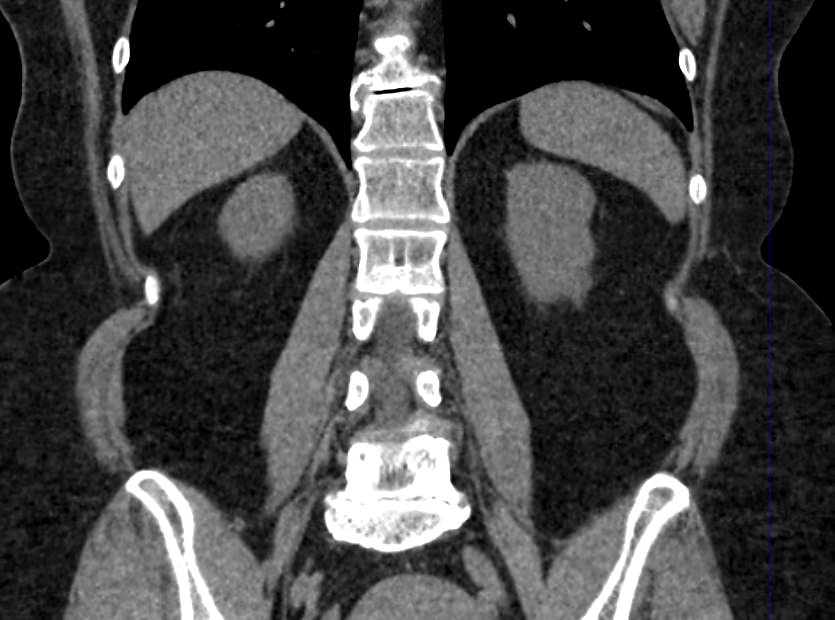

Мультиспиральная компьютерная томография (МСКТ) брюшной полости относится к современным лучевым методам исследования, с помощью которого можно оценить состояние органов брюшной полости (печени, желчного пузыря, поджелудочной железы, селезенки), прилегающих к ним кровеносных сосудов и лимфатических узлов.

С помощью мультиспиральной компьютерной томографии проводятся послойные рентгеновские снимки исследуемой области с толщиной среза от 0,5 мм. В нашей клинике исследование выполняется на компьютерном томографе экспертного класса TOSHIBA AQUILION CXL, который оснащен 128 детекторами, позволяющими получать за несколько секунд снимки брюшной полости с высокой точностью. Большое количество детекторов позволяет получить точные данные, при этом сократить время исследования и сделать минимальной лучевую нагрузку на пациента. Кроме того, инновационные технологии аппарата дают возможность сформировать объемную модель органа и окружающих структур, что также способствует проведению точной и достоверной диагностики.

При подозрении на опухоли, воспалительные процессы, гнойные очаги назначается КТ брюшной полости с внутривенным болюсным контрастированием. Для этого пациенту внутривенно вводится рентгеноконтрастное вещество на основе йода. Благодаря усиленному кровоснабжению препарат накапливается в структуре патологических образований и помогает врачу-рентгенологу выявить изменения в структуре внутренних органов.

Метод контрастирования помогает максимально точно выявить очаг патологии уже на начальной стадии, а также установить его локализацию, точные размеры, форму и особенности кровоснабжения.